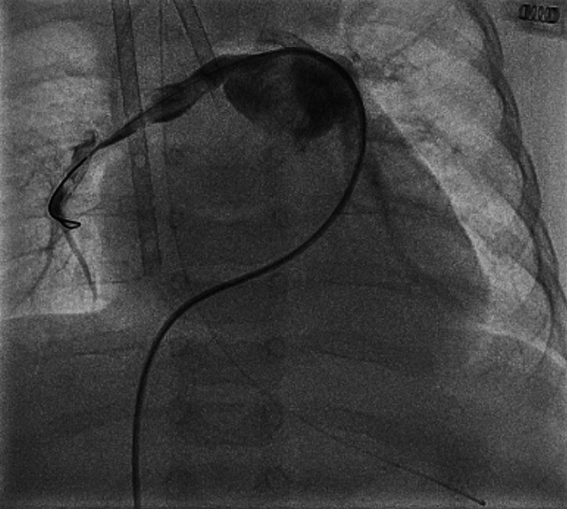

A 4-month-old infant (weight 5.2 kg, BSA 0.29 m2, oxygen saturation 84%) suffering from Tetralogy of Fallot (TOF), was referred for complete surgical repair at our institution. Diagnosis was made postnatally for development of cyanosis after birth. No comorbidities were present. Echocardiography showed a severe form of TOF with hypoplastic and dysplastic pulmonary valve of 3.5 mm of diameter with minimal anterograde blood flow and hypoplastic pulmonary branches of 2 mm of caliber. Continuous infusion of prostaglandin E was started, but urgent catheterization was needed because of progressive worsening of hypoxemia. A 6 mm stent was inserted in the right ventricular outflow tract (RVOT) (Fig. 1), with subsequent improvement of blood oxygenation, which allowed exstubation and home discharge. At the age of 4 months, the child underwent preoperative catheterization, which demonstrated good positioning of the previous stent, the pulmonary trunk of adequate caliber (10 mm), the right pulmonary artery (PA) of 4.6 mm, the left PA of 5 mm, and absence of severe stenoses in distal pulmonary branches (Fig. 2). Nakata index was 151 mm2/m2. After multidisciplinary evaluation, the patient was scheduled for complete surgical correction. Surgery was carried out on cardiopulmonary bypass (CPB). For RVOT reconstruction, a transannular homograft monocusped valve extended to the main pulmonary artery (MPA) was adopted (due to pulmonary valve entrapment in RVOT stent), the malaligned ventricular septal defect (VSD) was patch closed through a right atrial incision, the foramen ovale was left open. Pulmonary arteries (PAs) were probed and accepted a 5 mm Hegar. No intervention on PAs was performed. Extubation was possible on day 10th after resolution of transient right ventricular (RV) dysfunction due to junctional ectopic tachycardia and acute kidney injury requiring peritoneal dialysis. Postoperative echocardiography showed good reconstruction of MPA, but severe pulmonary regurgitation, and mild hypoplastic distal pulmonary branches. The patient was transferred to the ward on day 13th and maintained on prophylactic unfractionated heparin (UFH) 10 U/kg/h until right jugular central venous line removal on day 15th. The subsequent postoperative course was regular, with improving clinical status and nearly complete normalization of blood exams (see Table 1). On day 24th the patient presented sudden circulatory collapse requiring veno-arterial extracorporeal membrane oxygenation (VA-ECMO). Echocardiography showed severe RV dysfunction and absent blood flow through the right PA. Urgent diagnostic cardiac catheterization showed lack of contrast staining of the right PA suggestive of thrombosis (Fig. 3). Percutaneous thrombus fragmentation with multiple balloon dilations, local thrombolysis (Urokinase 4000 U/kg over 20 min), and aspiration were performed with partial thrombus removal and hemodynamic improvement. Continuous Urokinase infusion was not performed due to recent VA-ECMO cannulation. Following heart-team discussion, the patient was referred for surgical thrombus removal and concomitant central PAs enlargement plasty (Video 1): on CPB, MPA was transected and two thrombi were removed adopting the Fogarty technique (Fig. 4). Neither signs of intimal damage nor macroscopic focal arterial stenoses were noticed. Proximal right and left PAs enlargement plasty with heterologous pericardial patches was carried out (Fig. 5). An additional 3.5 mm opening was performed at the VSD patch. The patient was weaned from VA-ECMO easily in the operating room. Right ventricular function recovered gradually, with left-to-right shunting at the calibrated VSD, and estimated RV pressure equal to half of the systemic. Blood exams showed an isolated moderate increase in factor VIII activity and a slight decrease in factor IX and XI activity (see Table 1). Most frequent prothrombotic genetic polymorphisms were excluded (Leiden V factor and G20210A prothrombin gene mutation) and common inherited severe thrombophilia was ruled out (see Table 1). During hospital stay he was maintained on UFH increased to 20 U/kg/h and discharged home one month later on Warfarin (target INR 2-3) for six months, after hematological consultation. One-month control cardiac magnetic resonance revealed satisfactory PAs reconstruction and no thrombi were detected. Currently, the patient is in good clinical status and he had no relapse of thrombosis after discontinuation of anticoagulation therapy.

Fig. 1 Right ventricular outflow tract stenting at birth